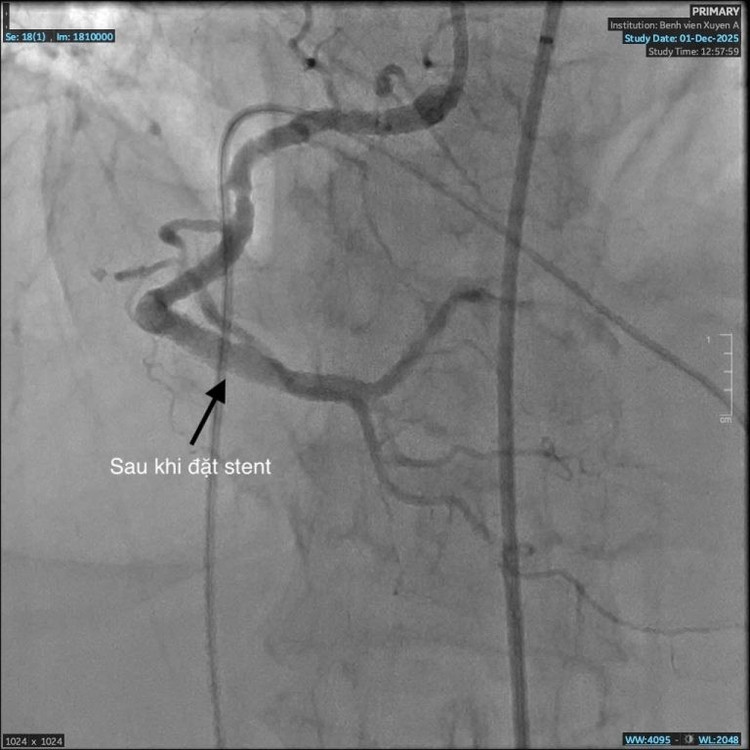

nhoi-mau-co-tim-4.jpg

Sau can thiệp stent, tái thông được mạch máu - Ảnh BVCC

Sau can thiệp, tình trạng huyết động của bệnh nhân dần ổn định, triệu chứng khó thở giảm rõ rệt, người bệnh qua cơn nguy kịch. Bệnh nhân tiếp tục được theo dõi sát và điều trị tích cực tại khoa Can thiệp Tim mạch, kết hợp kiểm soát các bệnh lý nền như tăng huyết áp, đái tháo đường và suy thận.